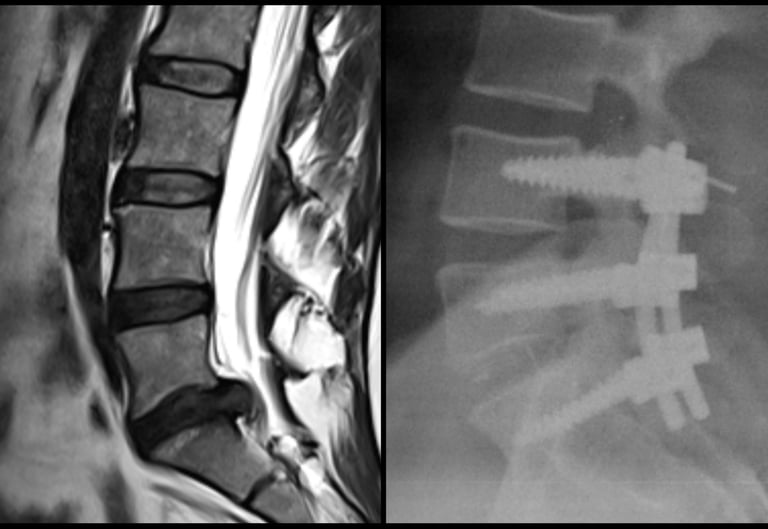

Artrodesis instrumentada, disectomia, cifoplastia, vertebroplastia, descompresion medular, liberacion radicular.